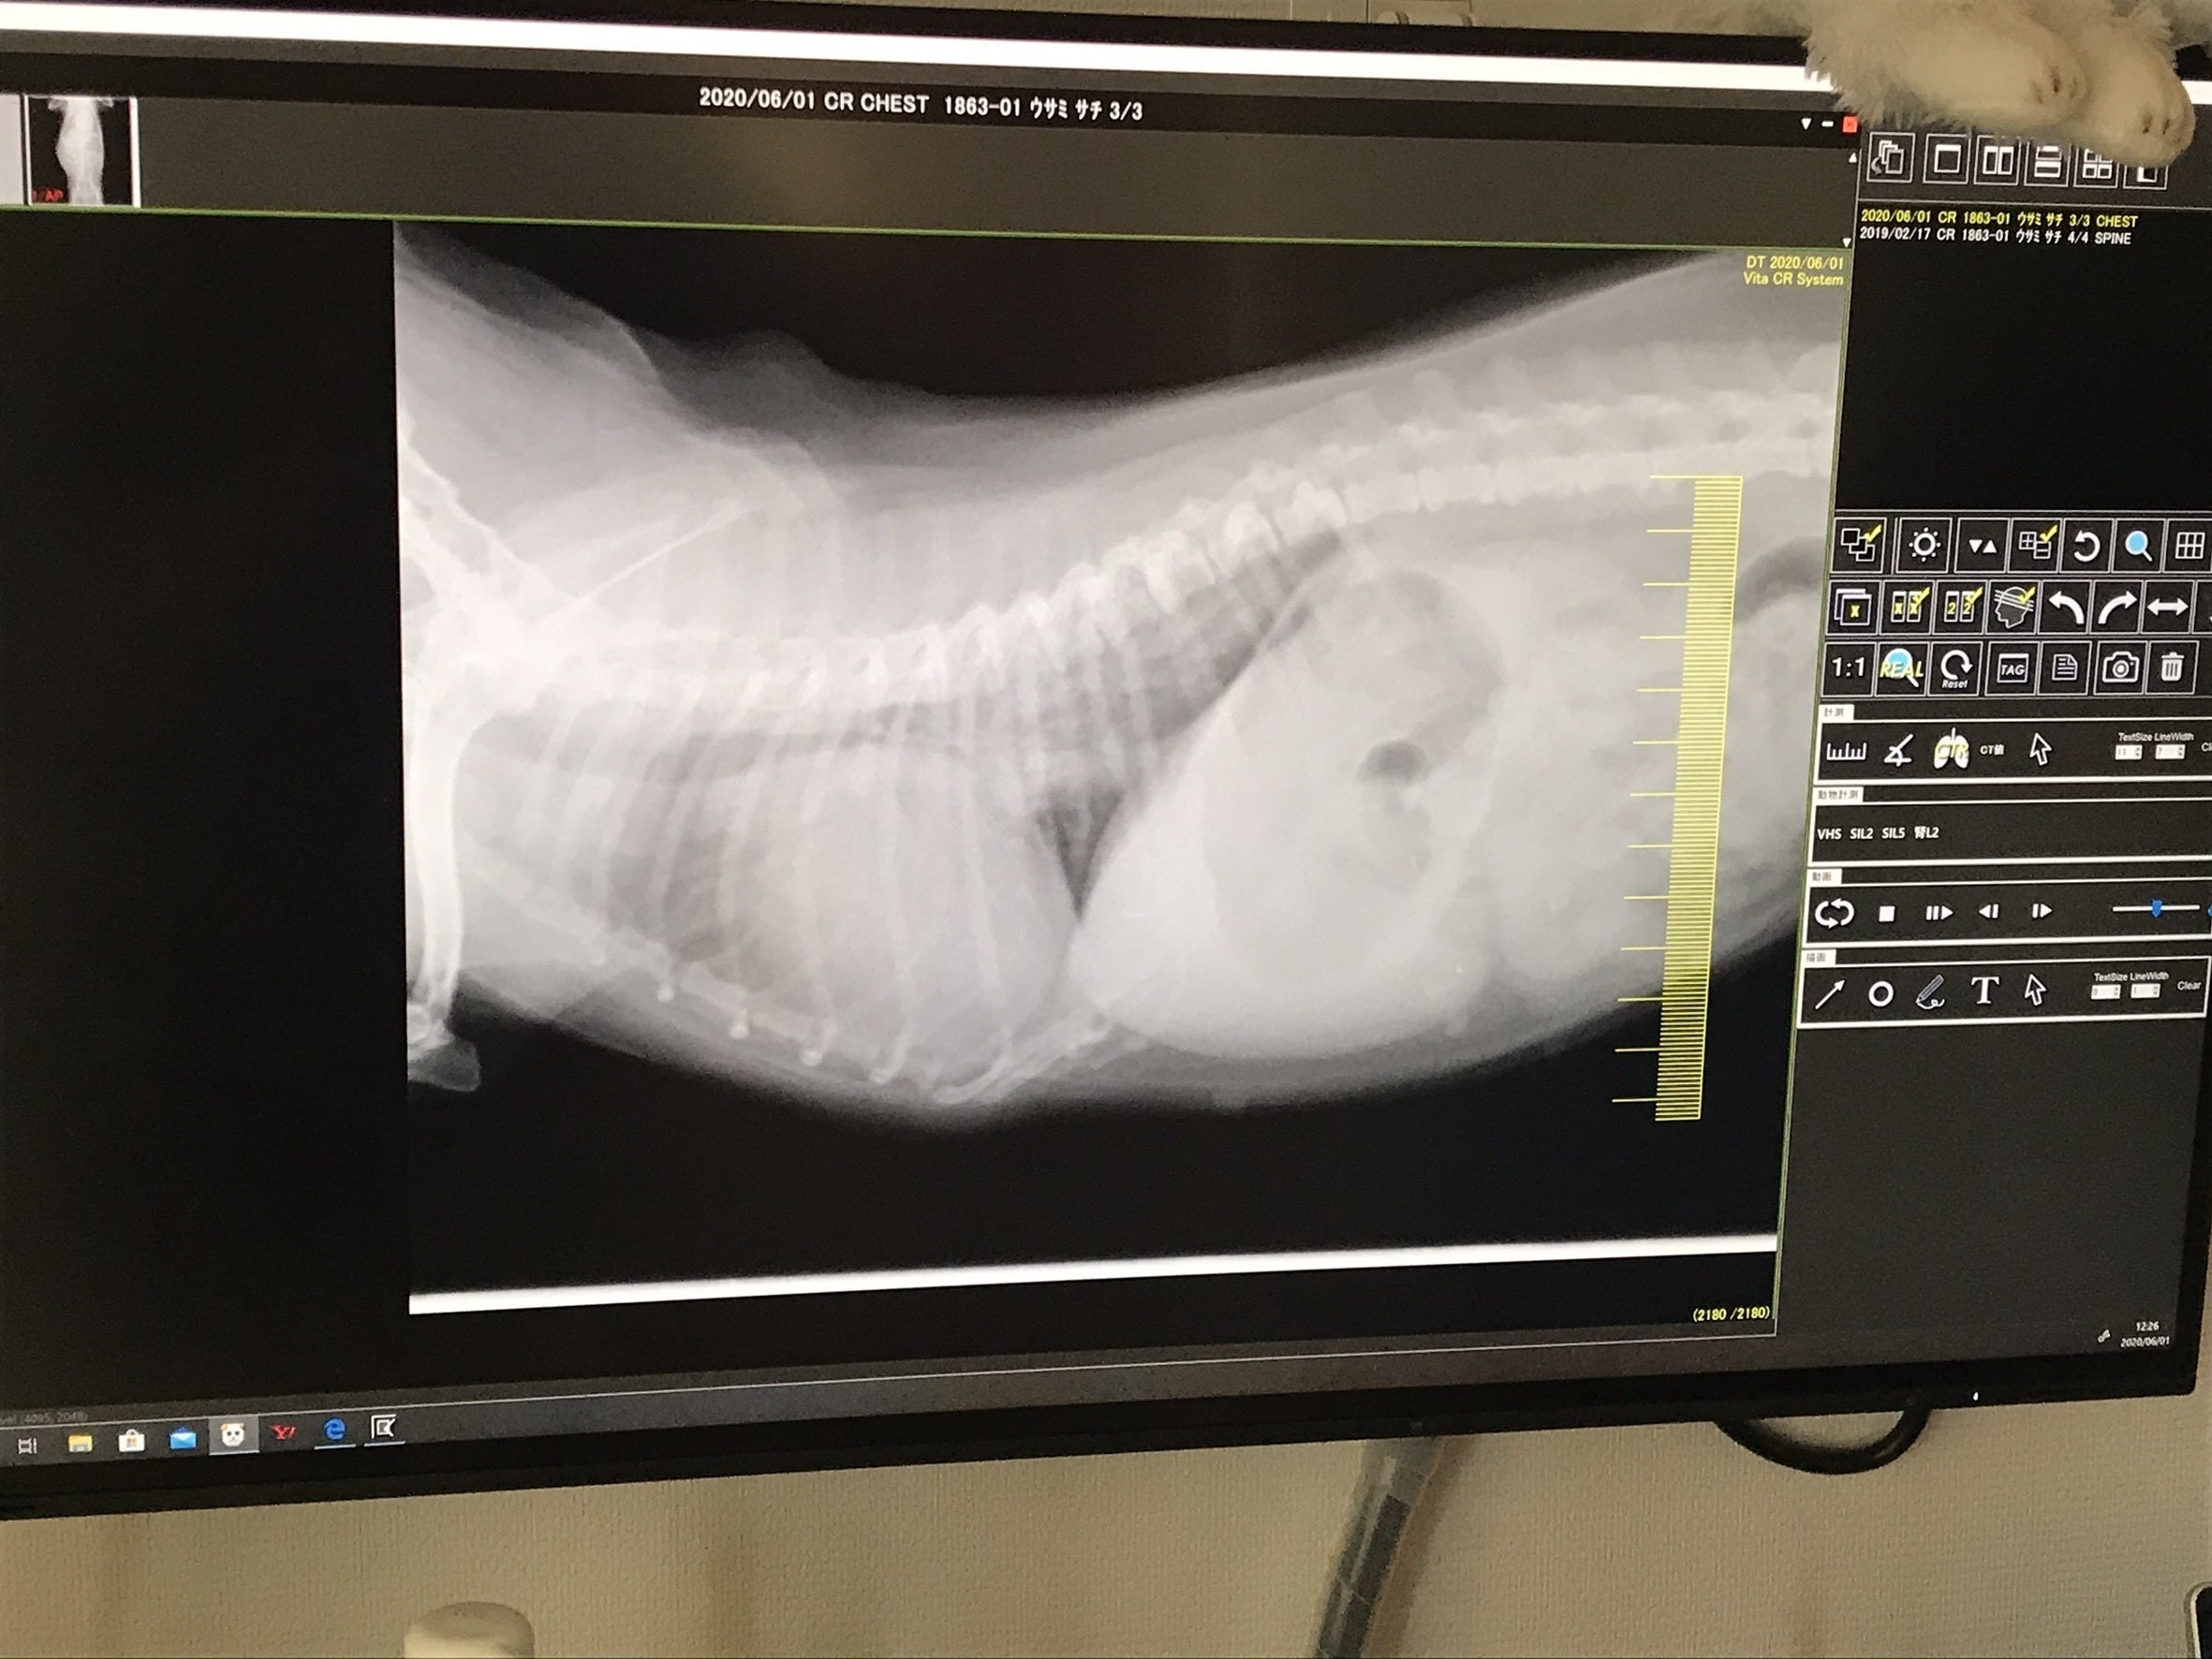

2020/6/1 初診

身体検査、血液検査、レントゲン撮影、酸素室治療を致しました。

この時点で心臓病と診断されました。

酸素室に4時間ほど入りお薬を頂きました。

次はレントゲン写真です。心臓が肥大して肺を圧迫しております。血液が逆流するため心臓により大きい負担がかかり、心不全や肺水腫などを引き起こします。この時点で肺水腫を起こし肺に水が溜まっておりました。